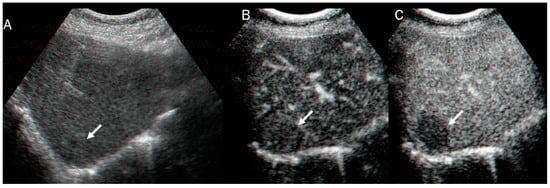

Figure 3.

US and CEUS assessment of ICC: On US (A), the lesion (arrow) shows iso-hypoechoic pattern compared to hepatic parenchymal. During arterial phase (B), the lesion shows arterial hyperenhancement (arrow), with washout (arrow) in portal phase (C).

In US studies, mass-forming ICC occurs as a large non-encapsulated mass with lobulated or variable shape. It can also be associated with liver capsule retraction and dilated peripheral bile ducts [80]. With respect to its pathomorphological characteristics (necrosis, fibrosis, and tumor growth), ICC can show a heterogeneous basal-US echogenicity pattern [81]. During CEUS assessment, ICC could show hyperenhancement during the arterial phase (Figure 3) with washout. According to several authors, ICC washout at its earliest stage is comparable to HCC, and this finding should guide a correct diagnosis [82,83,84].